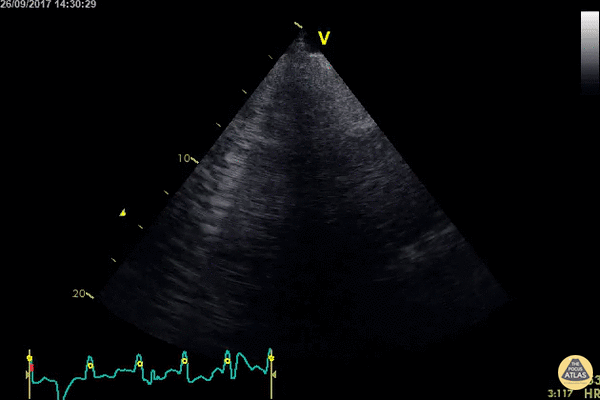

What sign is seen in this US?

D sign

Flattening of the interventricular septum, giving the left ventricle a D-shaped appearance in the parasternal short-axis view